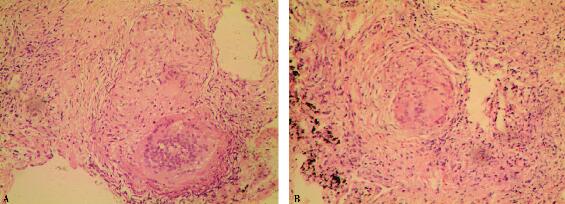

纤维支气管镜检查:双侧支气管及其各分支色泽、管口大小正常,未见结节、肿物;于右肺中叶灌洗,回收液似“牛奶样”,但PAS染色阴性;右肺上叶后段行肺活检,病理提示“类上皮细胞结节”(图2 HE×100)。

图2

为进一步明确诊断,该患者有经胸腔镜进行肺活检的指征。患者经胸腔镜进行肺活检病理结果提示:非干酪样坏死性类上皮细胞肉芽肿(图3A:HE×100,B:HE×200)、抗酸染色阴性。肺活检组织结核杆菌PCR检查阴性、真菌和结核菌培养均阴性。至此,终于明确诊断。

图3